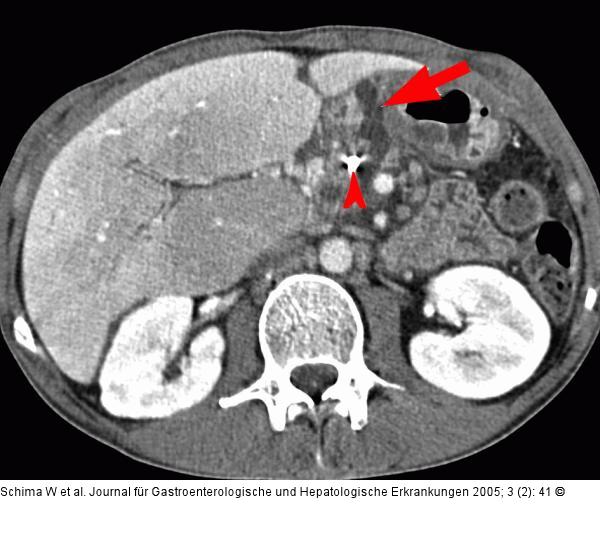

Abbildung 2a: Plastikstent - Pankreasnekrose Liegender Plastikstent (Pfeilspitze) und Pankreasnekrose mit Fistelbildung (Pfeil) |

Liegender Plastikstent (Pfeilspitze) und Pankreasnekrose mit Fistelbildung (Pfeil) |